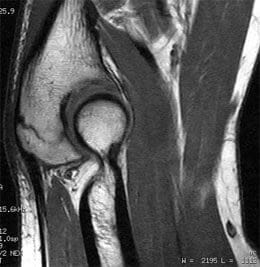

It went well. The doc says they didn’t need to take any cells from his pelvis. They got some from the other bone in his forearm (ulna). The damged bone (radius) is wired together again now, and will start on the the Pamindronate therapy in a couple of weeks.